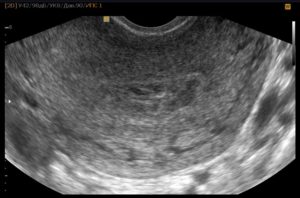

На таком сроке проводят ультразвуковой мониторинг с целью определения наступления овуляции. После менструации каждые 2-3 дня врач наблюдает за созреванием фолликулов и выходом яйцеклетки. На УЗИ определяется желтое тело.

Овуляция на УЗИ

Чаще всего на таком сроке беременности УЗИ не требуется, разве что есть необходимость оценить готовность эндометрия к зачатию. Аппарат в этот момент сможет исследовать и распознать доминирующий фолликул, но разглядеть яйцеклетку нет возможности.

Пройти такое обследование могут женщины, у которых уже были проблемы с зачатием, но планируют на данный момент беременность.

- УЗИ-мониторинг (ультразвуковой мониторинг). Самый достоверный метод определения выхода зрелой яйцеклетки из фолликула яичника, к которому в настоящее время прибегают многие женщины, планирующие беременность. При УЗИ-мониторинге можно назвать предположительный срок наступления овуляции, а не просто сделать вывод, что сегодня ее нет и вы уже опоздали. При нерегулярных циклах данный метод также помогает выявить причины задержки.